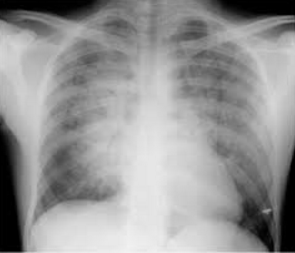

Triệu chứng cận lâm sàng:

- Làm điện tim

- Troponin tăng

- Rối loạn điện giải, áp lực thủy tĩnh máu

- Xét nghiệm men tuyến tụy: amylase, lipase

- Siêu âm tim: đánh giá chức năng van và chức năng thất trái, chức năng tâm trương khó được đánh giá, không loại trừ nguyên nhân do tim